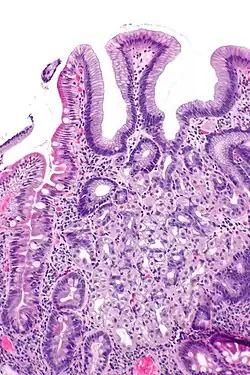

Mikrofoto einer Magenschleimhautheterotopie im Duodenum. HE-Färbung.

Heterotopie bedeutet in der Medizin funktionelles, also korrekt gebildetes und funktionierendes Gewebe, das sich nicht an der anatomisch üblichen Lokalisation befindet.[1]